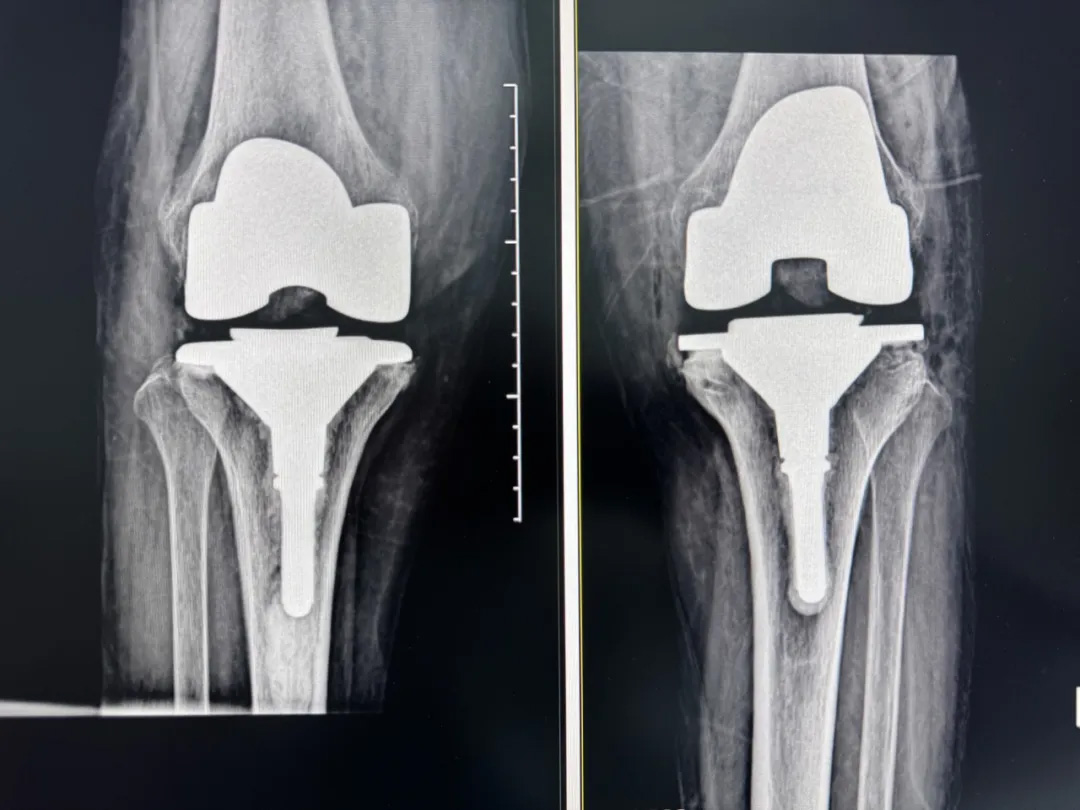

術(shù)前:AI通過(guò)CT掃描生成毫米級(jí)膝關(guān)節(jié)三維模型,為假體安裝設(shè)計(jì)出誤差小于1毫米的精準(zhǔn)方案 術(shù)中:智能導(dǎo)航系統(tǒng)如同"透視眼",引導(dǎo)醫(yī)生避開(kāi)密集的神經(jīng)血管網(wǎng),截骨更精準(zhǔn),出血僅100ml 術(shù)后:當(dāng)天鄭阿婆即開(kāi)始抬腿的康復(fù)訓(xùn)練,24小時(shí)內(nèi)扶助行器下地行走,三天后已能在病房走廊獨(dú)立行走,完成洗漱用餐 兩周后健步出院時(shí),女兒含淚感慨“之前擔(dān)心她年紀(jì)大扛不住手術(shù),沒(méi)想到恢復(fù)這么快!現(xiàn)在每天散步比我還精神。知道技術(shù)這么先進(jìn),真該早點(diǎn)來(lái)!”

"這就像給傳統(tǒng)手術(shù)裝上了自動(dòng)駕駛系統(tǒng)。"主刀醫(yī)生羅軍副院長(zhǎng)用生動(dòng)比喻解析技術(shù)突破。AI不僅實(shí)現(xiàn)假體“量身定制”,使用壽命可達(dá)20年以上,更通過(guò)三維路徑規(guī)劃將康復(fù)周期壓縮,實(shí)現(xiàn)術(shù)后24小時(shí)下地,2周回歸正常生活。同時(shí),AI會(huì)避開(kāi)重要組織,具有出血少、感染風(fēng)險(xiǎn)低的特點(diǎn)。專(zhuān)家特別提醒,當(dāng)出現(xiàn)夜間持續(xù)性關(guān)節(jié)疼痛、步行能力低于10分鐘或關(guān)節(jié)畸形時(shí),應(yīng)及時(shí)就醫(yī)評(píng)估,"別等到關(guān)節(jié)'報(bào)廢'才手術(shù)"。